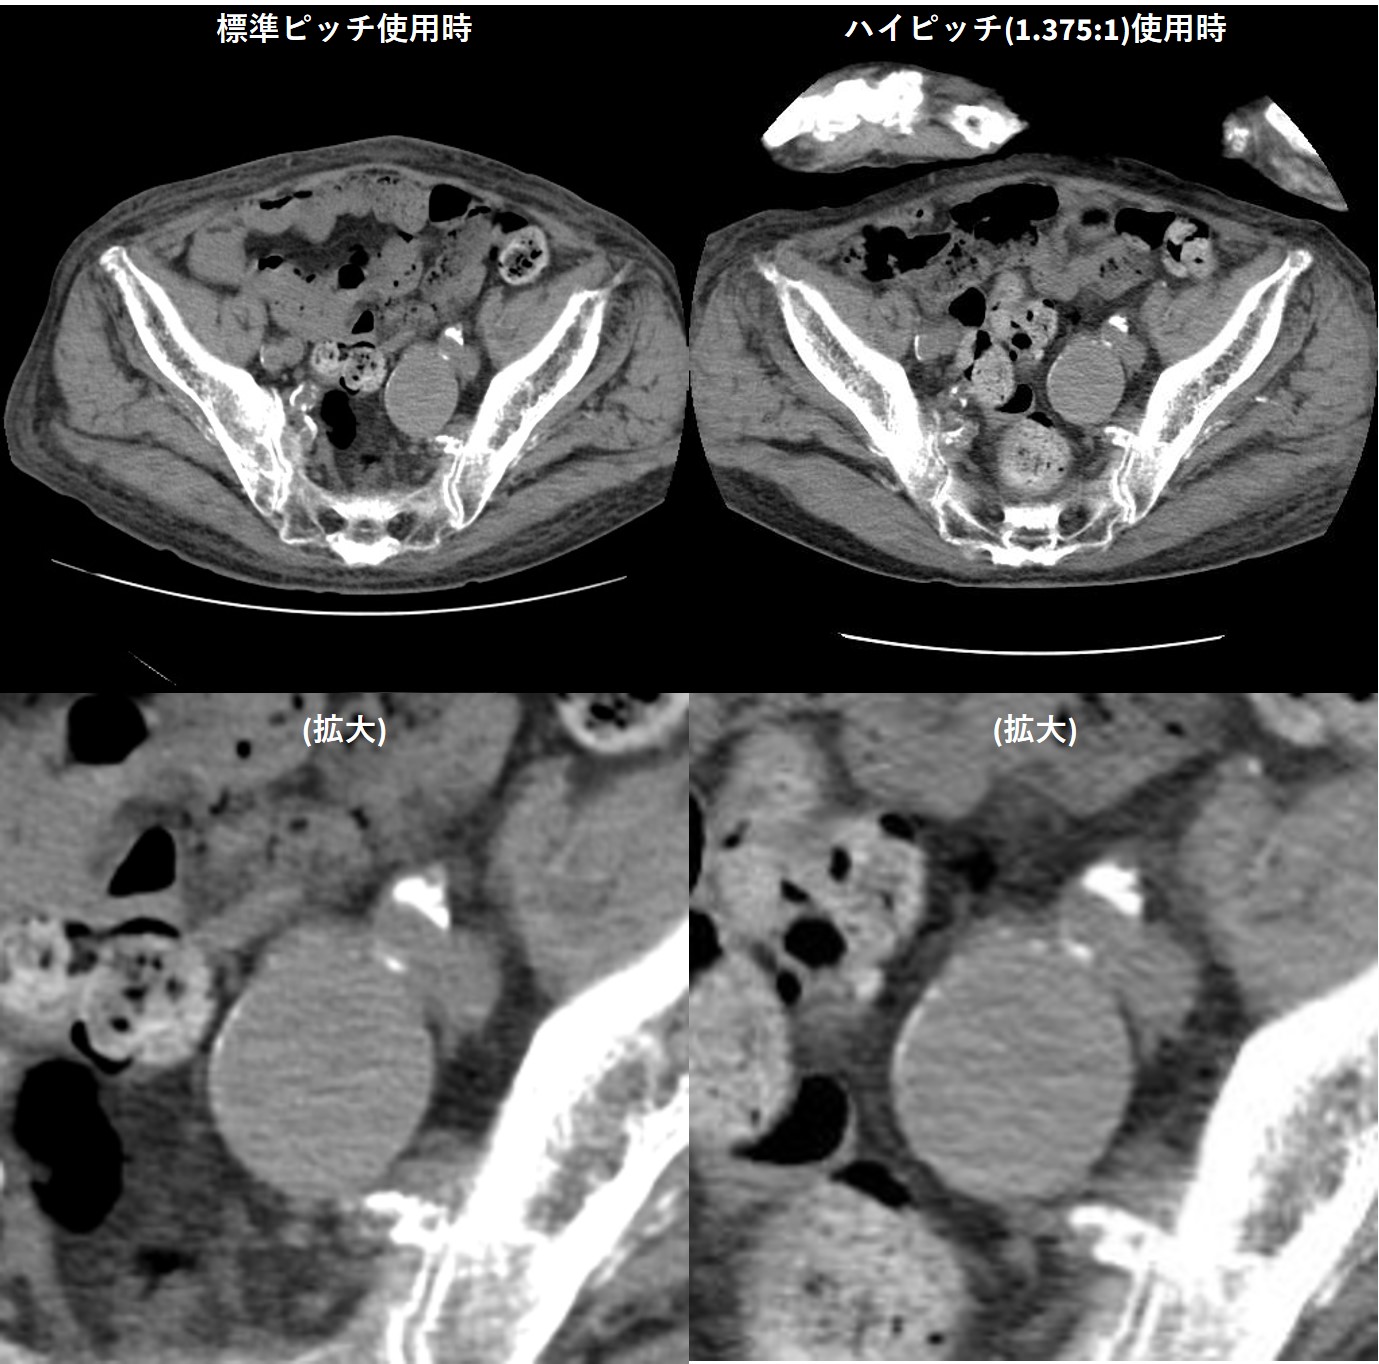

ハイピッチ使用時も 画質劣化が起きにくい

ハイピッチ使用時でも、画像を比較すると読影可能な画質を維持できている。図6の写真は左内腸骨動脈瘤の病変である。左側は患者が3か月に1回行っている定期フォロー時に撮影した通常ピッチ(0.984:1)の画像、右側は救急搬送時に撮影したハイピッチ(1.357:1)の画像であるが読影に影響が出る程の画質の差は感じられない。

Maxima_hachiojisanno10.jpg

図6 ピッチの違いによる左内腸骨動脈瘤の見え方の違い